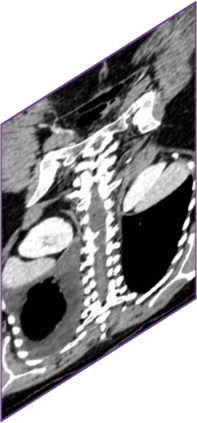

Due to the constraints of the imaging device and high cost in operation time, computer tomography (CT) scans are usually acquired with low intra-slice resolution. Improving the intra-slice resolution is beneficial to the disease diagnosis for both human experts and computer-aided systems. To this end, this paper builds a novel medical slice synthesis to increase the between-slice resolution. Considering that the ground-truth intermediate medical slices are always absent in clinical practice, we introduce the incremental cross-view mutual distillation strategy to accomplish this task in the self-supervised learning manner. Specifically, we model this problem from three different views: slice-wise interpolation from axial view and pixel-wise interpolation from coronal and sagittal views. Under this circumstance, the models learned from different views can distill valuable knowledge to guide the learning processes of each other. We can repeat this process to make the models synthesize intermediate slice data with increasing inter-slice resolution. To demonstrate the effectiveness of the proposed approach, we conduct comprehensive experiments on a large-scale CT dataset. Quantitative and qualitative comparison results show that our method outperforms state-of-the-art algorithms by clear margins.